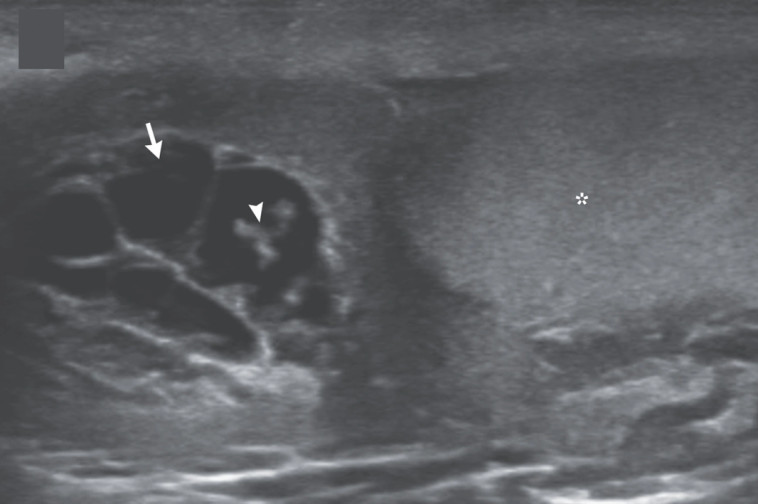

הוא אובחן עם "פילאריאזיס לימפטי" הידועה בשם אלפנטיאזיס - מחלה טרופית הנגרמת מעקיצת יתוש המדביק את החולה במין של תולעת עגולה מיקרוסקופית, כך על פי ארגון הבריאות העולמי. נמטודות זעירות גורמות לנוזל לחסום את מערכת הלימפה, ובאופן פרדוקסלי גורמות לשק האשכים ולחלקי גוף אחרים להתנפח ולהגיע לממדים דמויי פאכידרמה.

באשכיו של האיש ההודי התגלו תולעים זעירות שנדדו לתוך תעלות הלימפה וגרמו להתרבות. למטופל היה מזל שהרופאים גילו את מצבו העגום בזמן, מאחר ומחלה זו מתבטאת בשלבים מאוחרים יותר בנכויות קבועות. למרבה המזל, הרופאים הצליחו לפנות את הפולשות בעזרת טיפול שארך כשלושה שבועות בתרופה אנטי-טפילית.